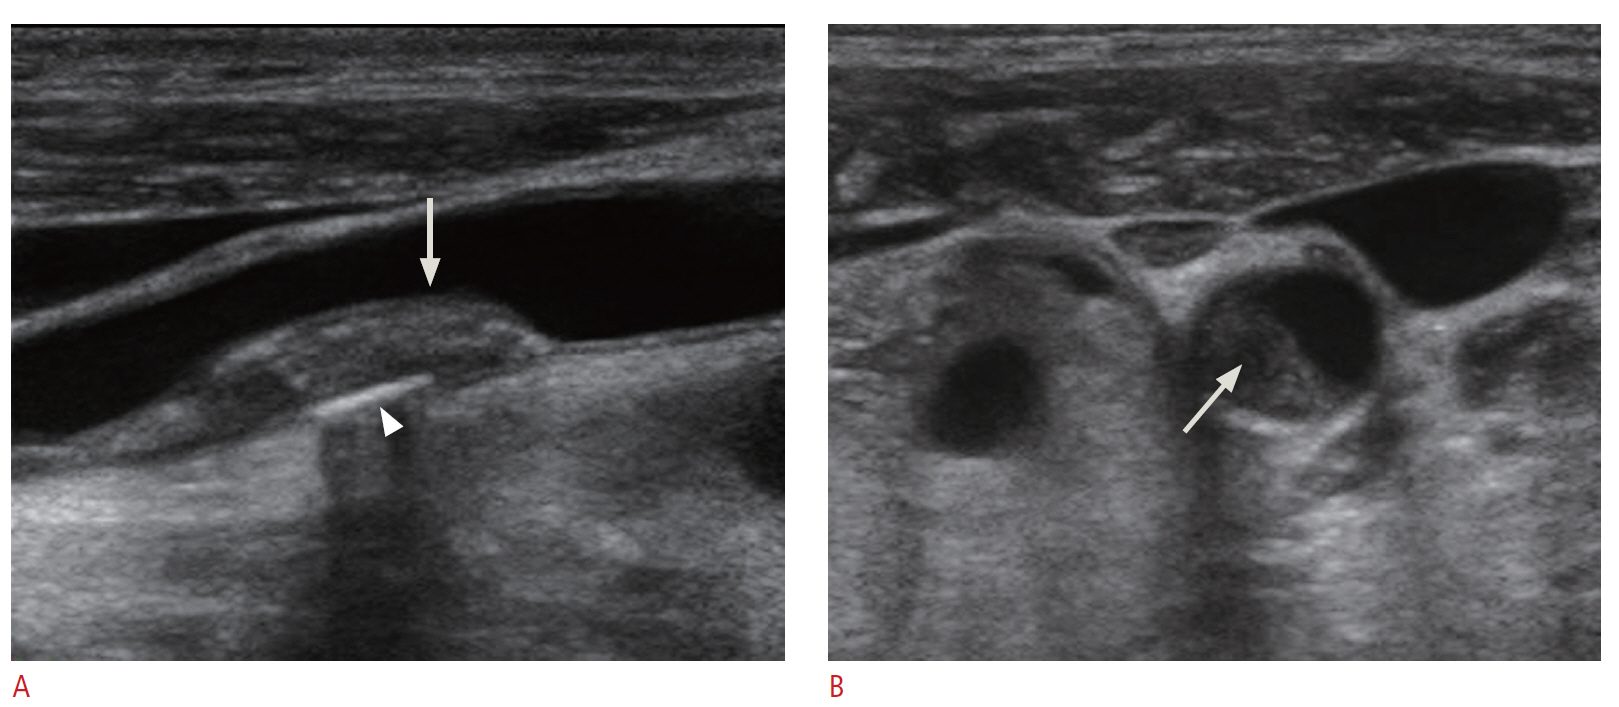

Carotid Doppler ultrasonography is a popular tool for evaluating atherosclerosis of the carotid artery. Its two-dimensional gray scale can be used for measuring the intima-media thickness, which is very good biomarker for atherosclerosis and can aid in plaque characterization. The plaque morphology is related to the risk of stroke. The ulceration of plaque is also known as one of the strong predictors of future embolic event risk. Color Doppler ultrasonography and pulse Doppler ultrasonography have been used for detecting carotid artery stenosis. Doppler ultrasonography has unique physical properties. The operator should be familiar with the physics and other parameters of Doppler ultrasonography to perform optimal Doppler ultrasonography studies.